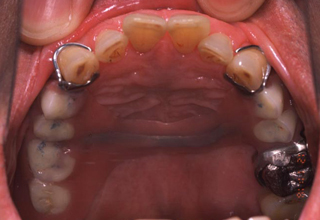

初診時の口腔内写真 主訴を考慮した保険の義歯

図1a

図1aは初診時に話しづらさと装着時の違和感を訴え来院した患者の義歯装着時の口腔内写真である. 図1bは、保険の義歯ではあるが、この主訴を考慮し装着した義歯である。

発音については舌の動きを阻害しないよう,また装着感については大連結子の形状や走行,義歯床縁の形態を配慮した。